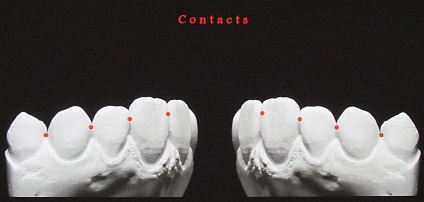

Klinikailag jelentős átmenetek vannak érintkezési felületek a vestibularis és száj felületén.

Az átmenet az érintkező felületek a vesztibuláris a henger felületét képez kellően hangsúlyos korlátozó reflexió zónában. Ez a zóna korlátozott, kivéve a marginális gerincek, és az egyenlítő a korona és a vágás.

A kapcsolattartó pontok között, a felső elülső fogak elrendezve egy görbe mentén, megismételve a hajlam a vágóélek a felső és alsó ajak kontúr. Ha az érintkezési pont között a metszőfogak és a szemfogak vetített középvonalában, akkor hogy három szinten egy pályát körülbelül 1 mm.

Található egy ív mentén, a felső elülső fogak érintkeznek egymással csak orális felületeken, így fogközökbõl mindig legyen látható arci széle egybeesik a felület síkja terület gondolkodás, és ezért beeső fény és harmonikusan együtt. Hiánya metszőfogak a hajlamok olyan közös fény visszaverése orálisan (opistognatiya) vagy vesztibuláris (prognathia) vezet disbalance holisztikus felfogása a tervezési egység. Elmélkedés a fényviszonyok, így a fogak élénkebb és kifejezőbb észlelés mások nem csak abban az esetben könnyű fogakat, hanem ha a központi zóna reflexív fogak, mint homorú parabolatükörre vagy a felső oldalsó metszőfogak található a gépen a középső metszőfog, ha a trapéz alakú fogazat.

Az elülső fogak érintkeznek egymással az orális felületek, mivel vannak elrendezve egy ív. Következésképpen a kapcsolattartó pontok az elülső fogak mindig nyitott a vesztibuláris oldalon. Ez segít a helyreállítása elülső fogak, hogy újra a hatása családi fogak korona, képeznek egységes fogazat. Ezzel szemben, ennek elmulasztása azt eredményezi, a helyreállítás egy mesterséges növelése keresztirányú mérete koronák és létrehozza a vizuális hatás a „szilárd fehér fal” figyelhető meg a helyreállítás konstrukciók, ahol a koronák összekapcsolt (híd, amely a rúd szerkezet, fém ív).